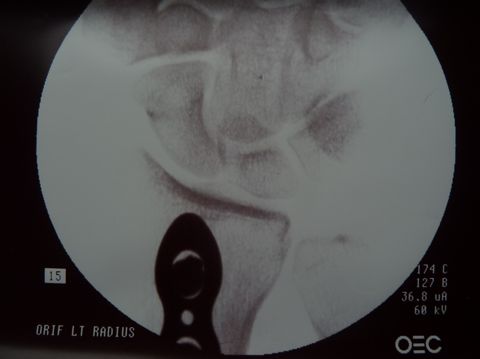

Dr. Gray used flouroscopy to confirm that the fracture margins were in perfect alignment, secured by three screws proximal and three screws distal to the fracture. |

| In fact, one view (below right) shows such tight apposition and such perfect alignment, that one cannot even see the fracture margins. | |

Dr. Gray checked all of her wrist bones (left), applied a new plaster splint and a new sling, and Alison's I.V. line was removed about 2.5 hours after it was inserted. What a great surgeon and professional team! |